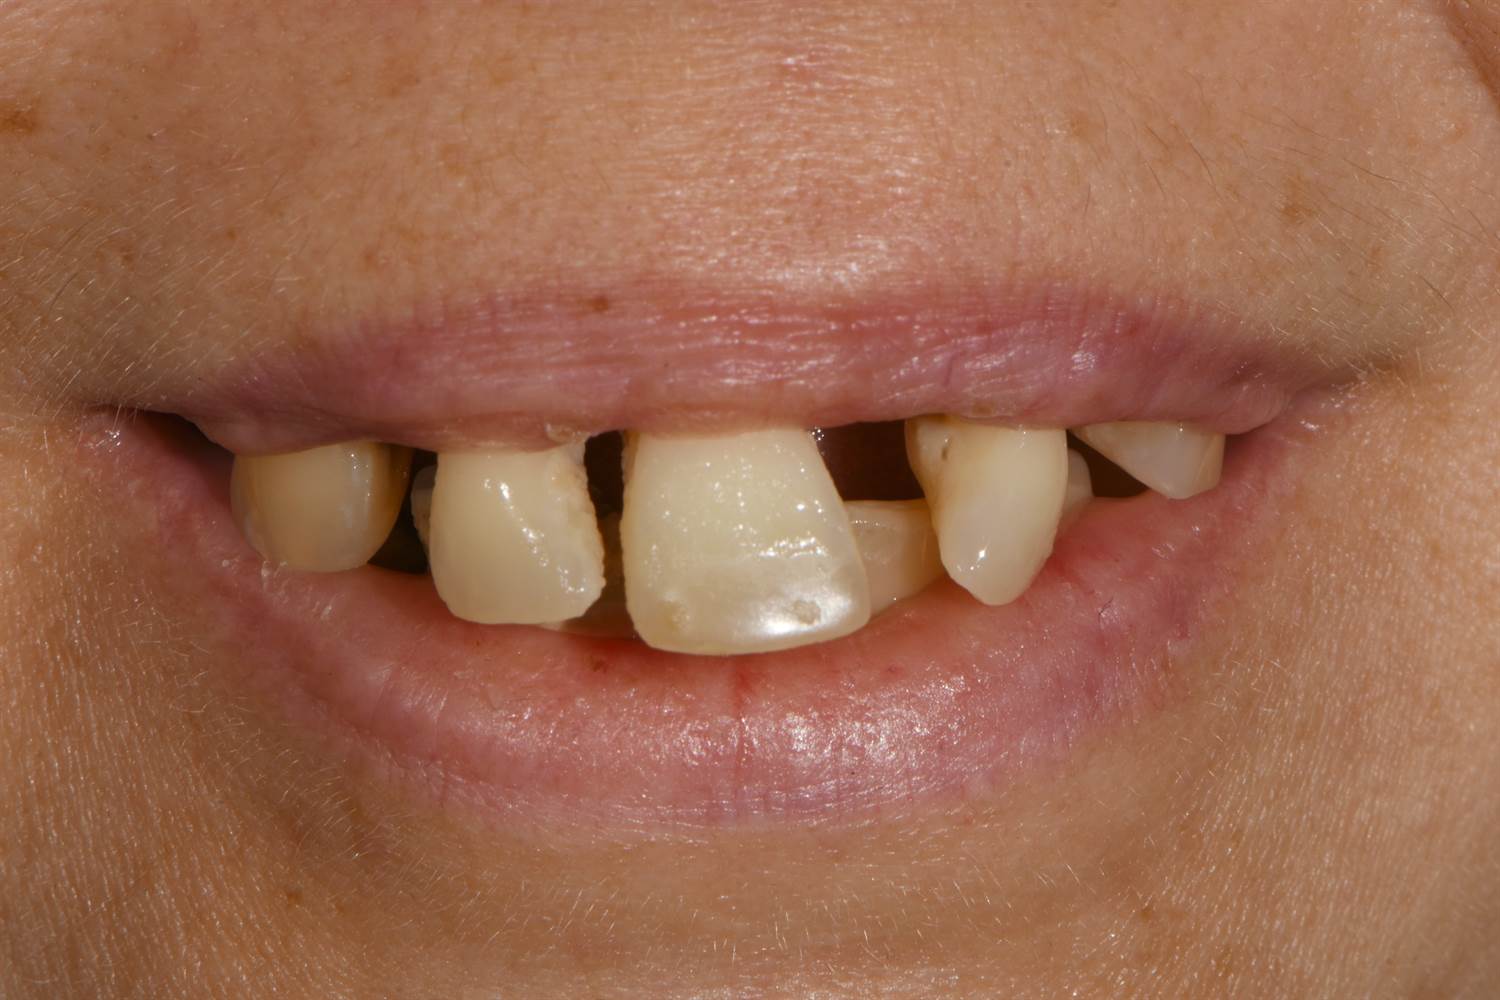

All-on-4® terapija namijenjena je osobama koje su izgubile većinu ili sve zube u jednoj čeljusti ili pacijentima koji nose mobilne proteze i žele stabilnije i dugoročnije rješenje. Ova metoda omogućuje rekonstrukciju potpunog zubnog niza i povratak normalnoj funkciji žvakanja, govora i osmijeha.

imate zube koji se više ne mogu spasiti

Prikaz stvarnih rezultata postignutih All-on-4® terapijom kod naših pacijenata.